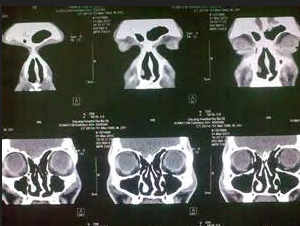

圖:鼻中隔偏曲CT